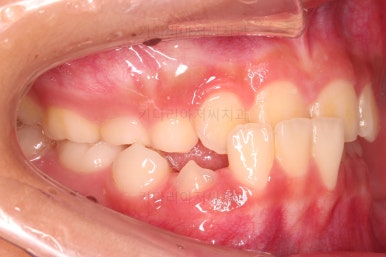

Case 2. 전/후

CASE 2.

바로 부산어린이교정 전후사진 비교해 볼게요.

단, 2주만에 문제시 되는 딱 한 개의 치아에만 포커스를 맞춰 해당 치아 반대교합만 개선해준 매우 훌륭한 치료였습니다.

이상 매우 간단한 장치로 매우 빠르게 반대교합을 치료한 부산어린이교정 두 명의 치료사례였습니다.